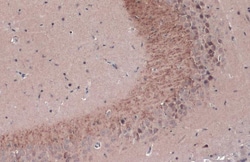

Keep as concentrated solution. Predicted reactivity: Mouse (100%), Rat (100%), Dog (100%), Cat (100%), Pig (100%), Chimpanzee (100%), Bovine (100%). Positive Control: mouse brain, rat brain, BDNF-transfected 293T. Store product as a concentrated solution. Centrifuge briefly prior to opening the vial.

| Immunohistochemistry (Frozen), Immunohistochemistry (Paraffin), Western Blot, Immunocytochemistry | |